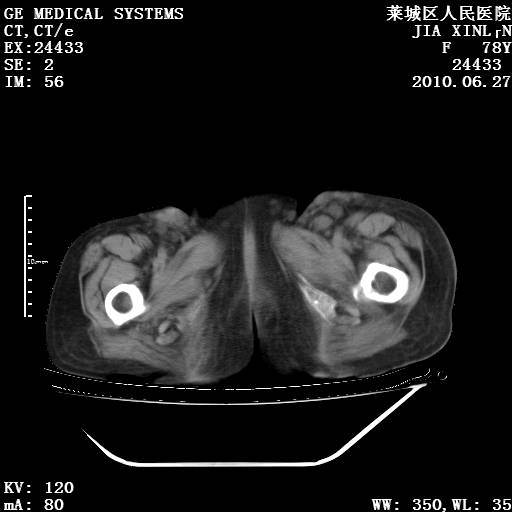

以下是引用胡宇在2010-7-2 19:11:00的发言:[br]神经纤维瘤的特点为:肿块呈多发性、数目不定,少的几个,多的可成百上千难以计数。小的如米粒,大的似拳头,甚至可达十数公斤以上。可松弛地悬挂于皮表,皱褶及松弛可致畸形明显。神经纤维瘤沿神经干的走向生长时呈念珠状,或蚯蚓块状形结节。此外神经纤维瘤皮肤可出现咖啡斑,大小不一,形如雀斑小点状,或大片状,分布与神经纤维瘤肿块的分布无关。肿瘤数目不多的患者,皮肤色素咖啡斑状沉着是纤维神经瘤的重要诊断之一。 本病多发于躯干,有时出现于四肢及面部,患者常合并许多疾病应予重视加以区别。 [br] [br] [br] [br]lyb999说 [br]